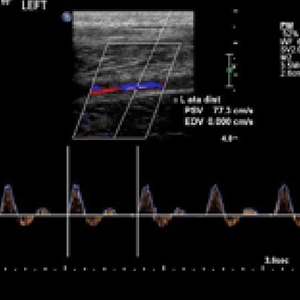

Rules out peripheral arterial disease. More than half of the population with cornonary artery disease has peripheral arterial disease, yet less than 20% of the patients are checked